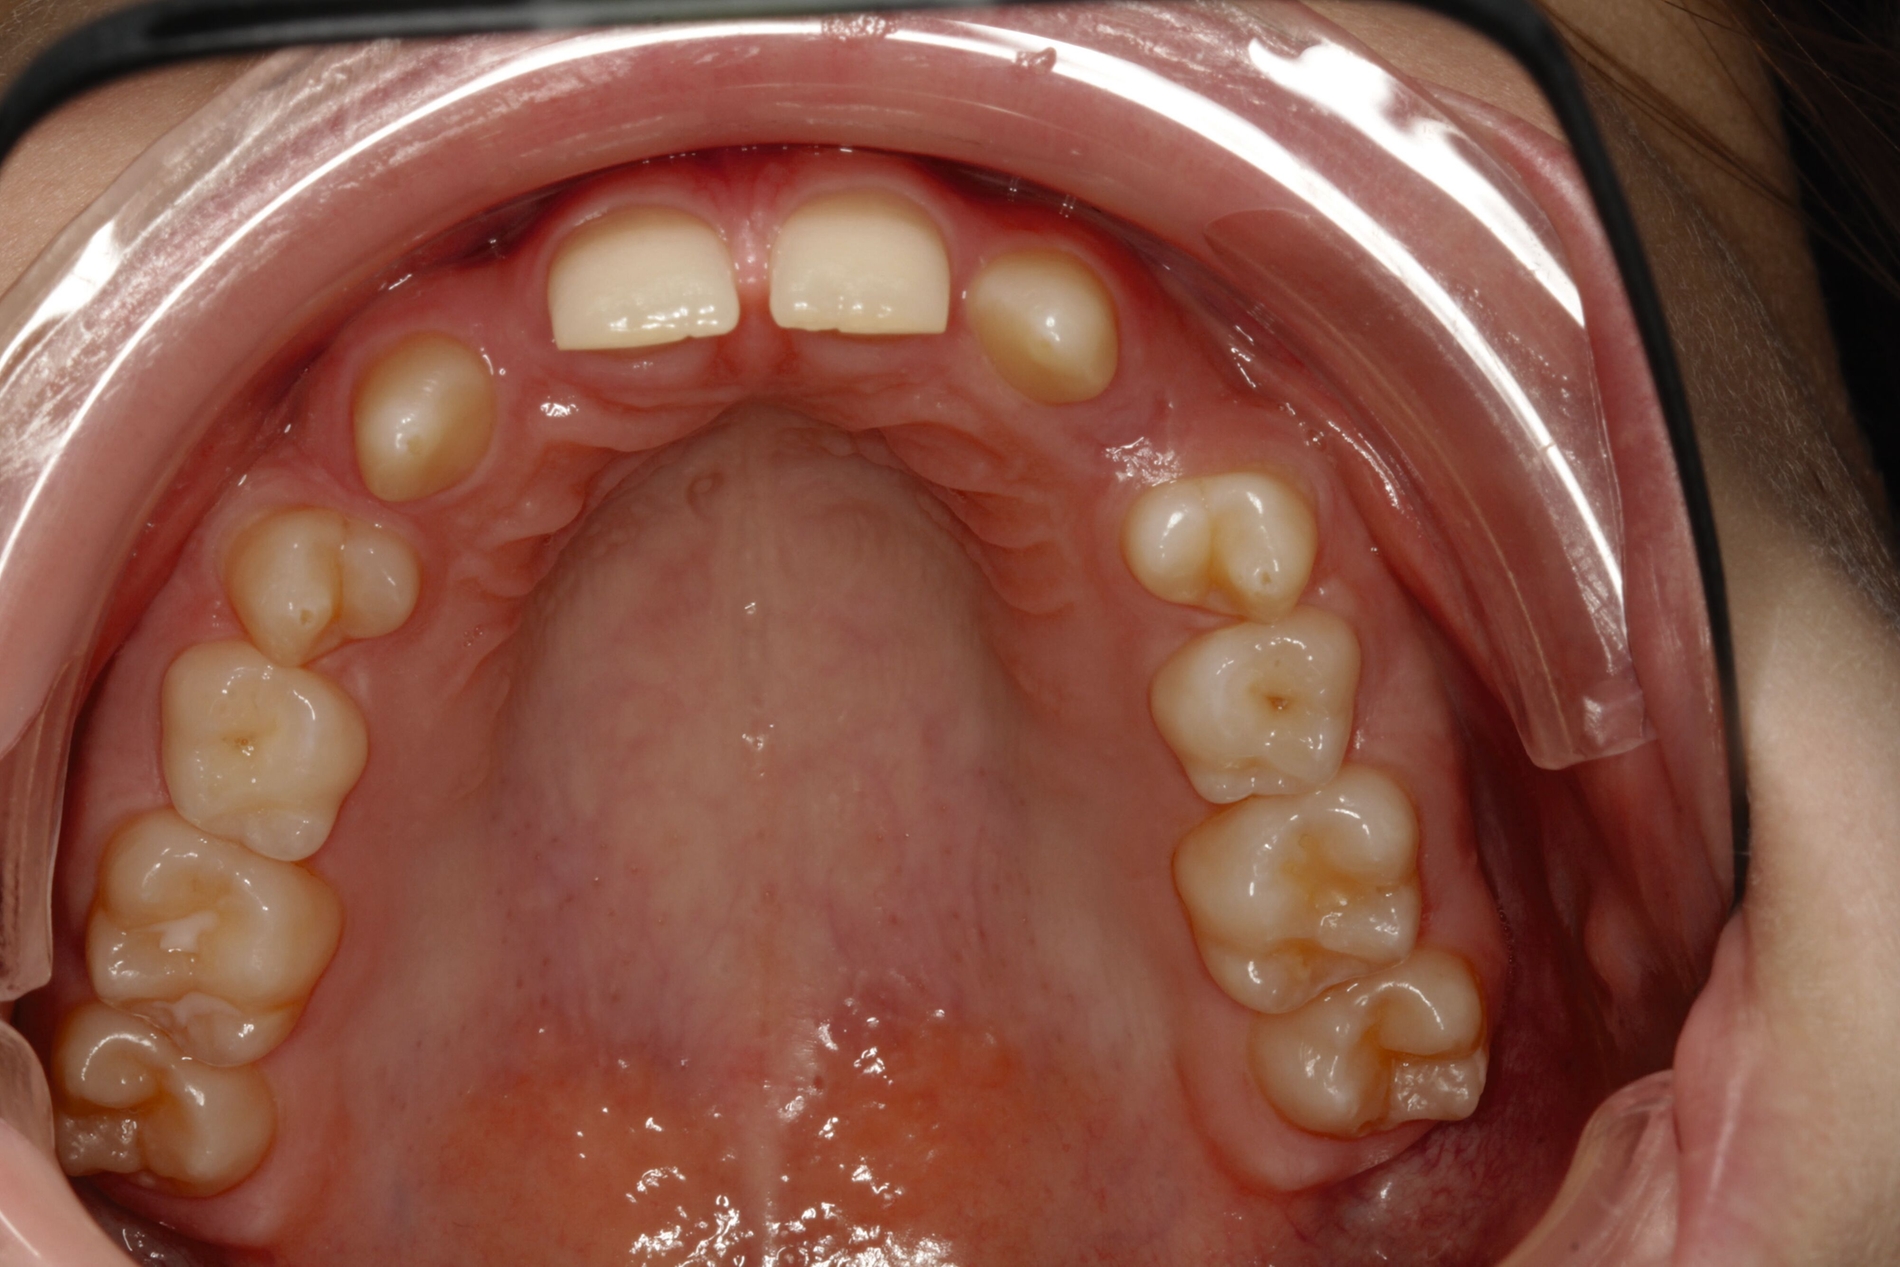

Bei dem gut zwölfjährigen Mädchen sind die seitlichen oberen Schneidezähne (Zähne 12 und 22) nicht angelegt. Zusätzlich zeigten sich verlagerte zweite obere Prämolaren.